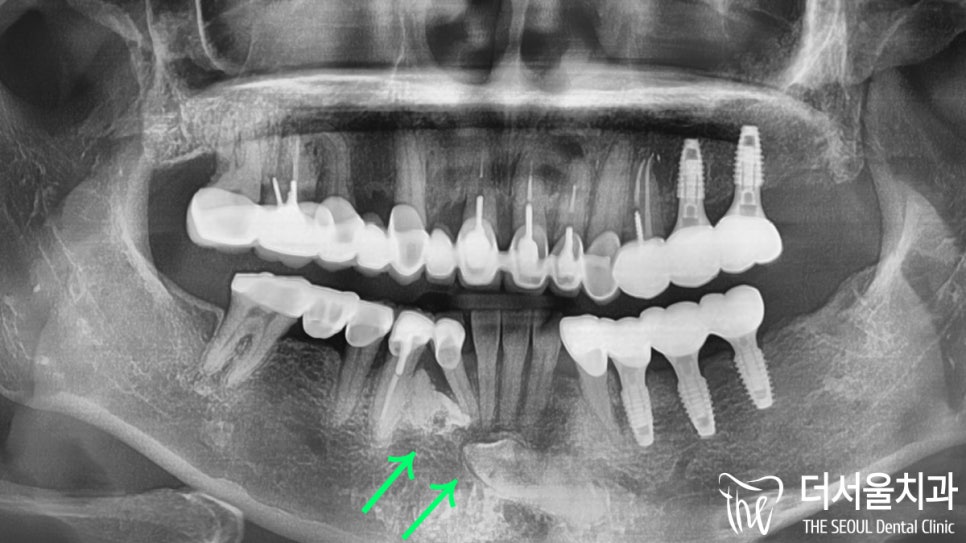

문제는.. 이게 다가 아니었습니다.

바로 # 43 하방의 과잉치였는데요.

사실 예전에 치료받았던 곳에서

이 과잉치 때문에 인공치아를 심을 수 없다면서

브릿지로 진행을 하셨다네요.

흠.. 그렇지만 이제는 자연치가 더는

버틸 수 없을 거란 생각이 들었습니다.